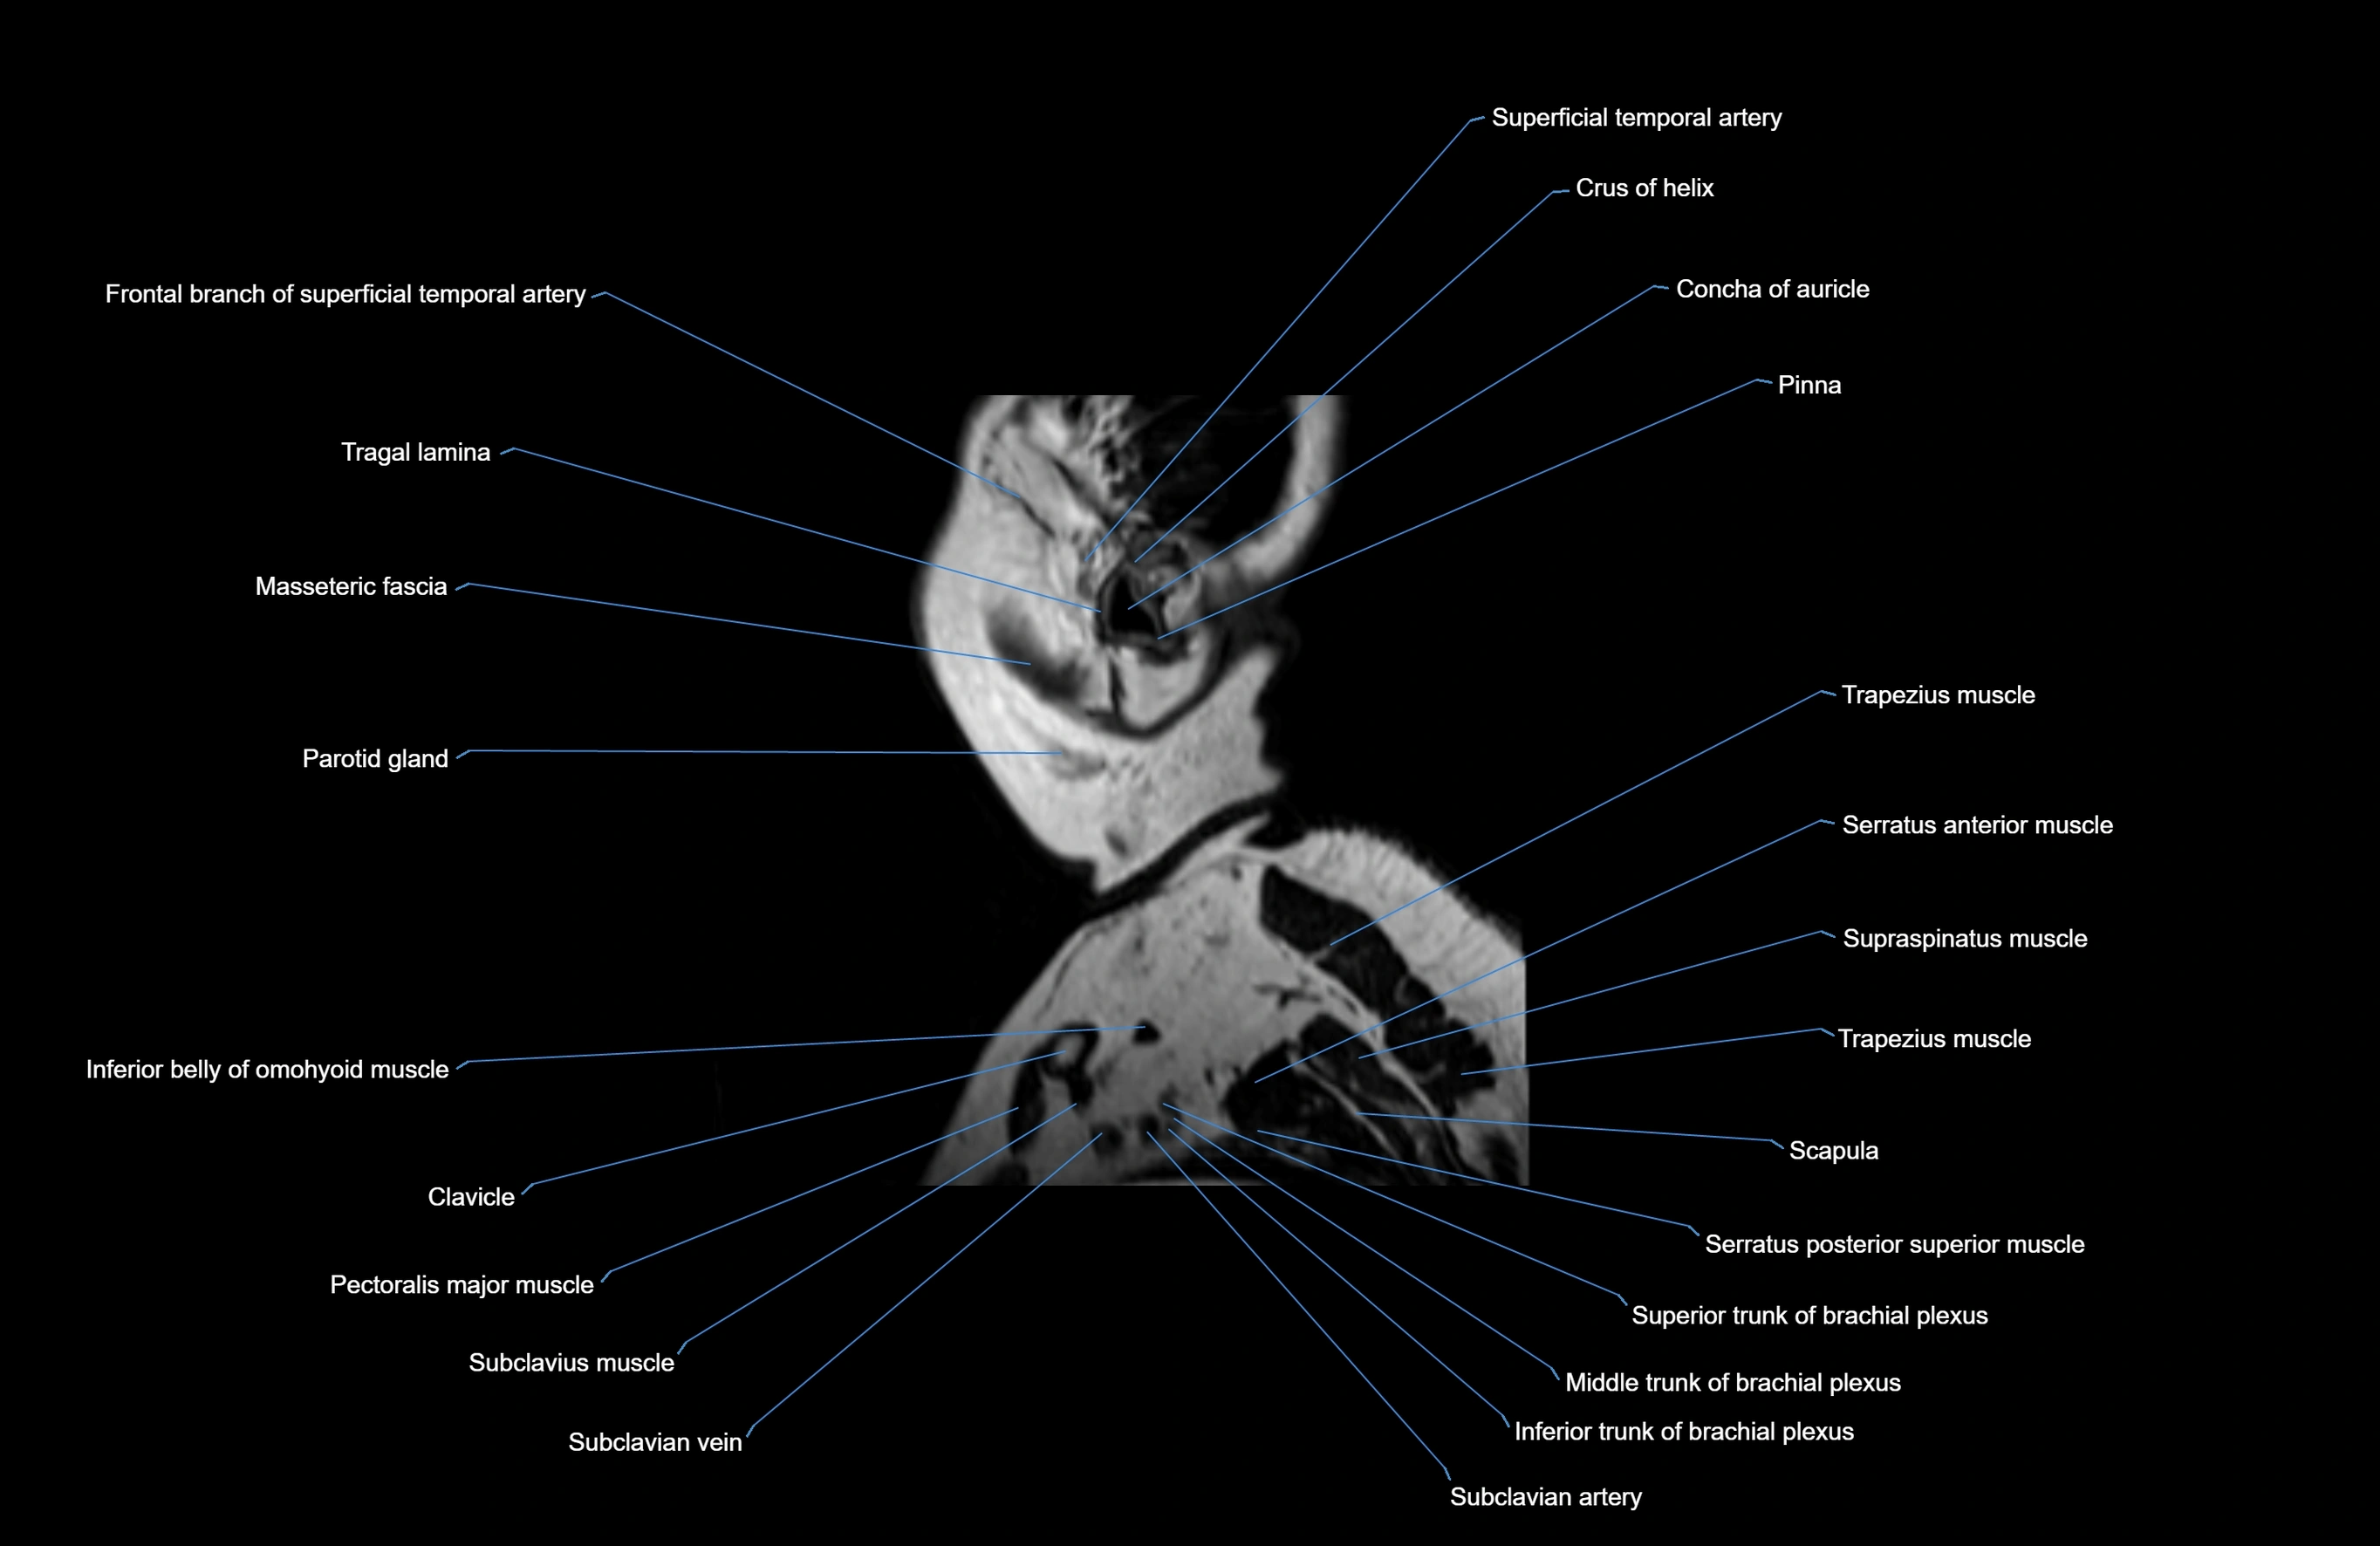

MRI images